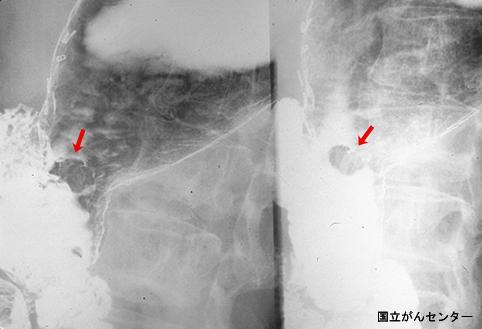

Cancer Precoz de Estómago de tipo Protruído tipo I aparecido en el residual

Tokyo Pref., Centro Nacional de curaciones de Cáncer, Hospital Central y Centro Kyusyu de Curaciones de Cáncerc

Tumor Epitelial Maligno/Adenocarcinoma

estómago(región)/cuerpo

Rayos X

Tipo 0(tipo superficial)/Tipo I(I)

15 - 19

m